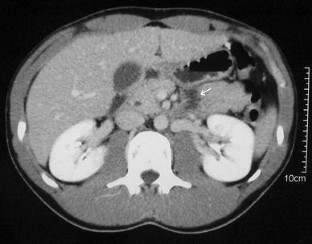

Eleven patients (2 with grade I injury, 3 with grade II injury, and 6 with grade III injury, all diagnosed by contrast-enhanced helical CT) were included. Nonsurgical management was carried out in all of these patients. Among grade III patients, one developed a peripancreatic abscess; another, a pancreatic fistula. Both were successfully treated nonoperatively. The average length of hospital stay was similar in grade I-II and grade III patients. After a median follow-up of 57 months no mortality or pancreatic sequelae had occurred.

Fig. 3